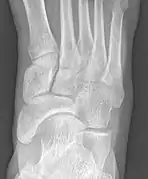

From left to right: Type 1, 2 and 3